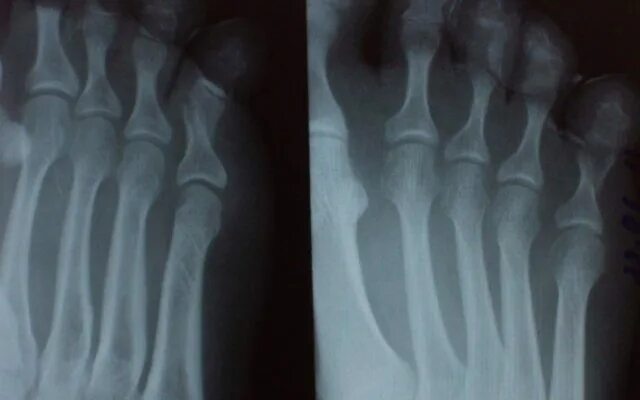

Закрытый перелом пальцев стопы мкб 10